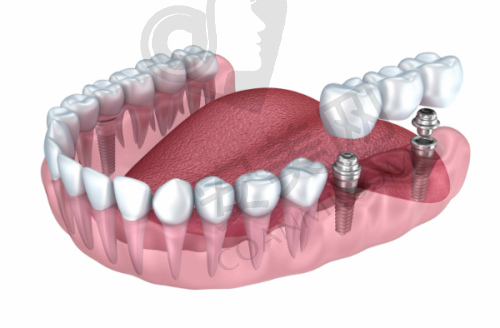

美国皓圣种植牙是一种非常受欢迎的种植牙系统。它采用了精良的材料和技术,具有以下几个显著的优势。首先,美国皓圣种植牙的种植体表面经过特殊处理,能够与人体骨组织更好地结合,提高种植体的稳定性和成功几率。其次,该种植系统的设计符合人体口腔生理结构,能够更好地修复牙齿的咀嚼功能和美观度。患者在种植后,几乎感觉不到与自然牙的差异,能够正常饮食和生活。此外,美国皓圣种植牙的使用寿命较长,只要患者做好口腔护理,一般可以使用特别长时间。而且,这种种植牙的维护相对简单,患者只需要按照医生的建议进行日常口腔清洁和定期复查即可。

患者到深圳新浩口腔做美国皓圣种植牙,首先需要进行全方面的口腔检查。医生会通过口腔CT等设备,详细了解患者的牙槽骨情况、牙齿缺失情况以及口腔健康状况。根据检查结果,庄贤安医生会为患者制定个性化的种植方案,并向患者详细解释种植过程、可能出现的问题以及术后的注意事项等。如果患者同意种植方案,就可以进行种植手术。在手术前,医生会对患者进行局部麻醉,以减轻手术过程中的疼痛。手术过程中,医生会将种植体植入牙槽骨内,然后缝合创口。术后,患者需要按照医生的嘱咐进行护理,如服用消炎药、避免食用实力强的食物等。一般在种植体与牙槽骨结合稳定后,医生会为患者安装牙冠,至此整个种植牙过程就完成了。